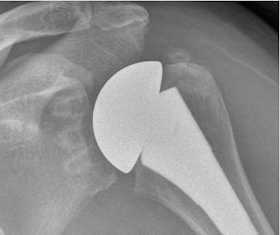

A case example from this paper shows late loosening of an initially well-fixed glenoid component

This is the type of component loosening that has been associated with rotator cuff failure via the 'rocking horse' mechanism.